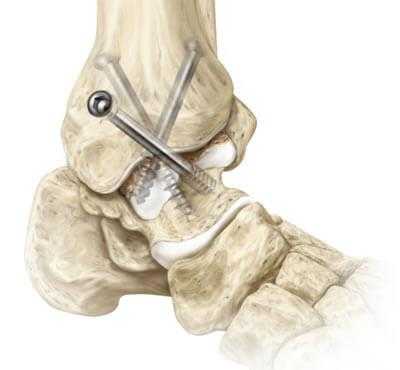

В Геленк Клинике применяются различные пластические методики. При пластике внешней связки её пытаются восстановить с помощью импланта из собственной ткани. Для этого используются остаточные элементы, части надкостницы латеральной лодыжки и ткани суставной капсулы. Если этих тканей недостаточно, то используются имплантаты сухожилий. Для этого изымаются части, проходящие в непосредственной близости от внешней связки, и затем пересаживаются в сустав.

Хирурги Геленк Клиники проводят восстановление голеностопного сустава при хронической нестабильности по методу Brostöm. При этом оставшиеся элементы служат для анатомического восстановления. Во время операции они собираются, а затем растягиваются, чтобы достичь первоначальной длины связок. Для обеспечения стабильности, части разгибательных сухожилий перемещаются в сторону латеральной лодыжки и сшиваются.